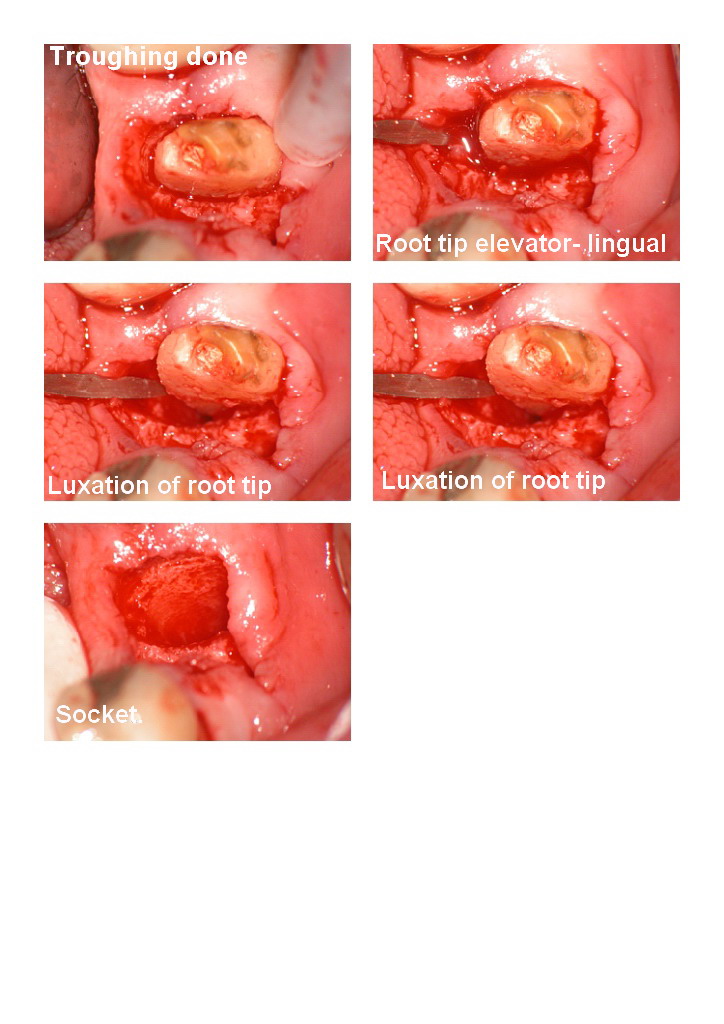

It was an extraction of a fractured crown which couldnt be restored.

Hope you like it.

Glenn

PS think how hard it would be to photograph this case traditionally.